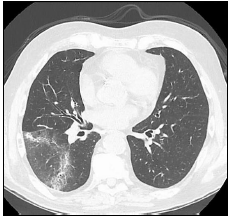

Observe a imagem de uma tomografia torácica:

A imagem possui um sinal que é altamente sugestivo de: